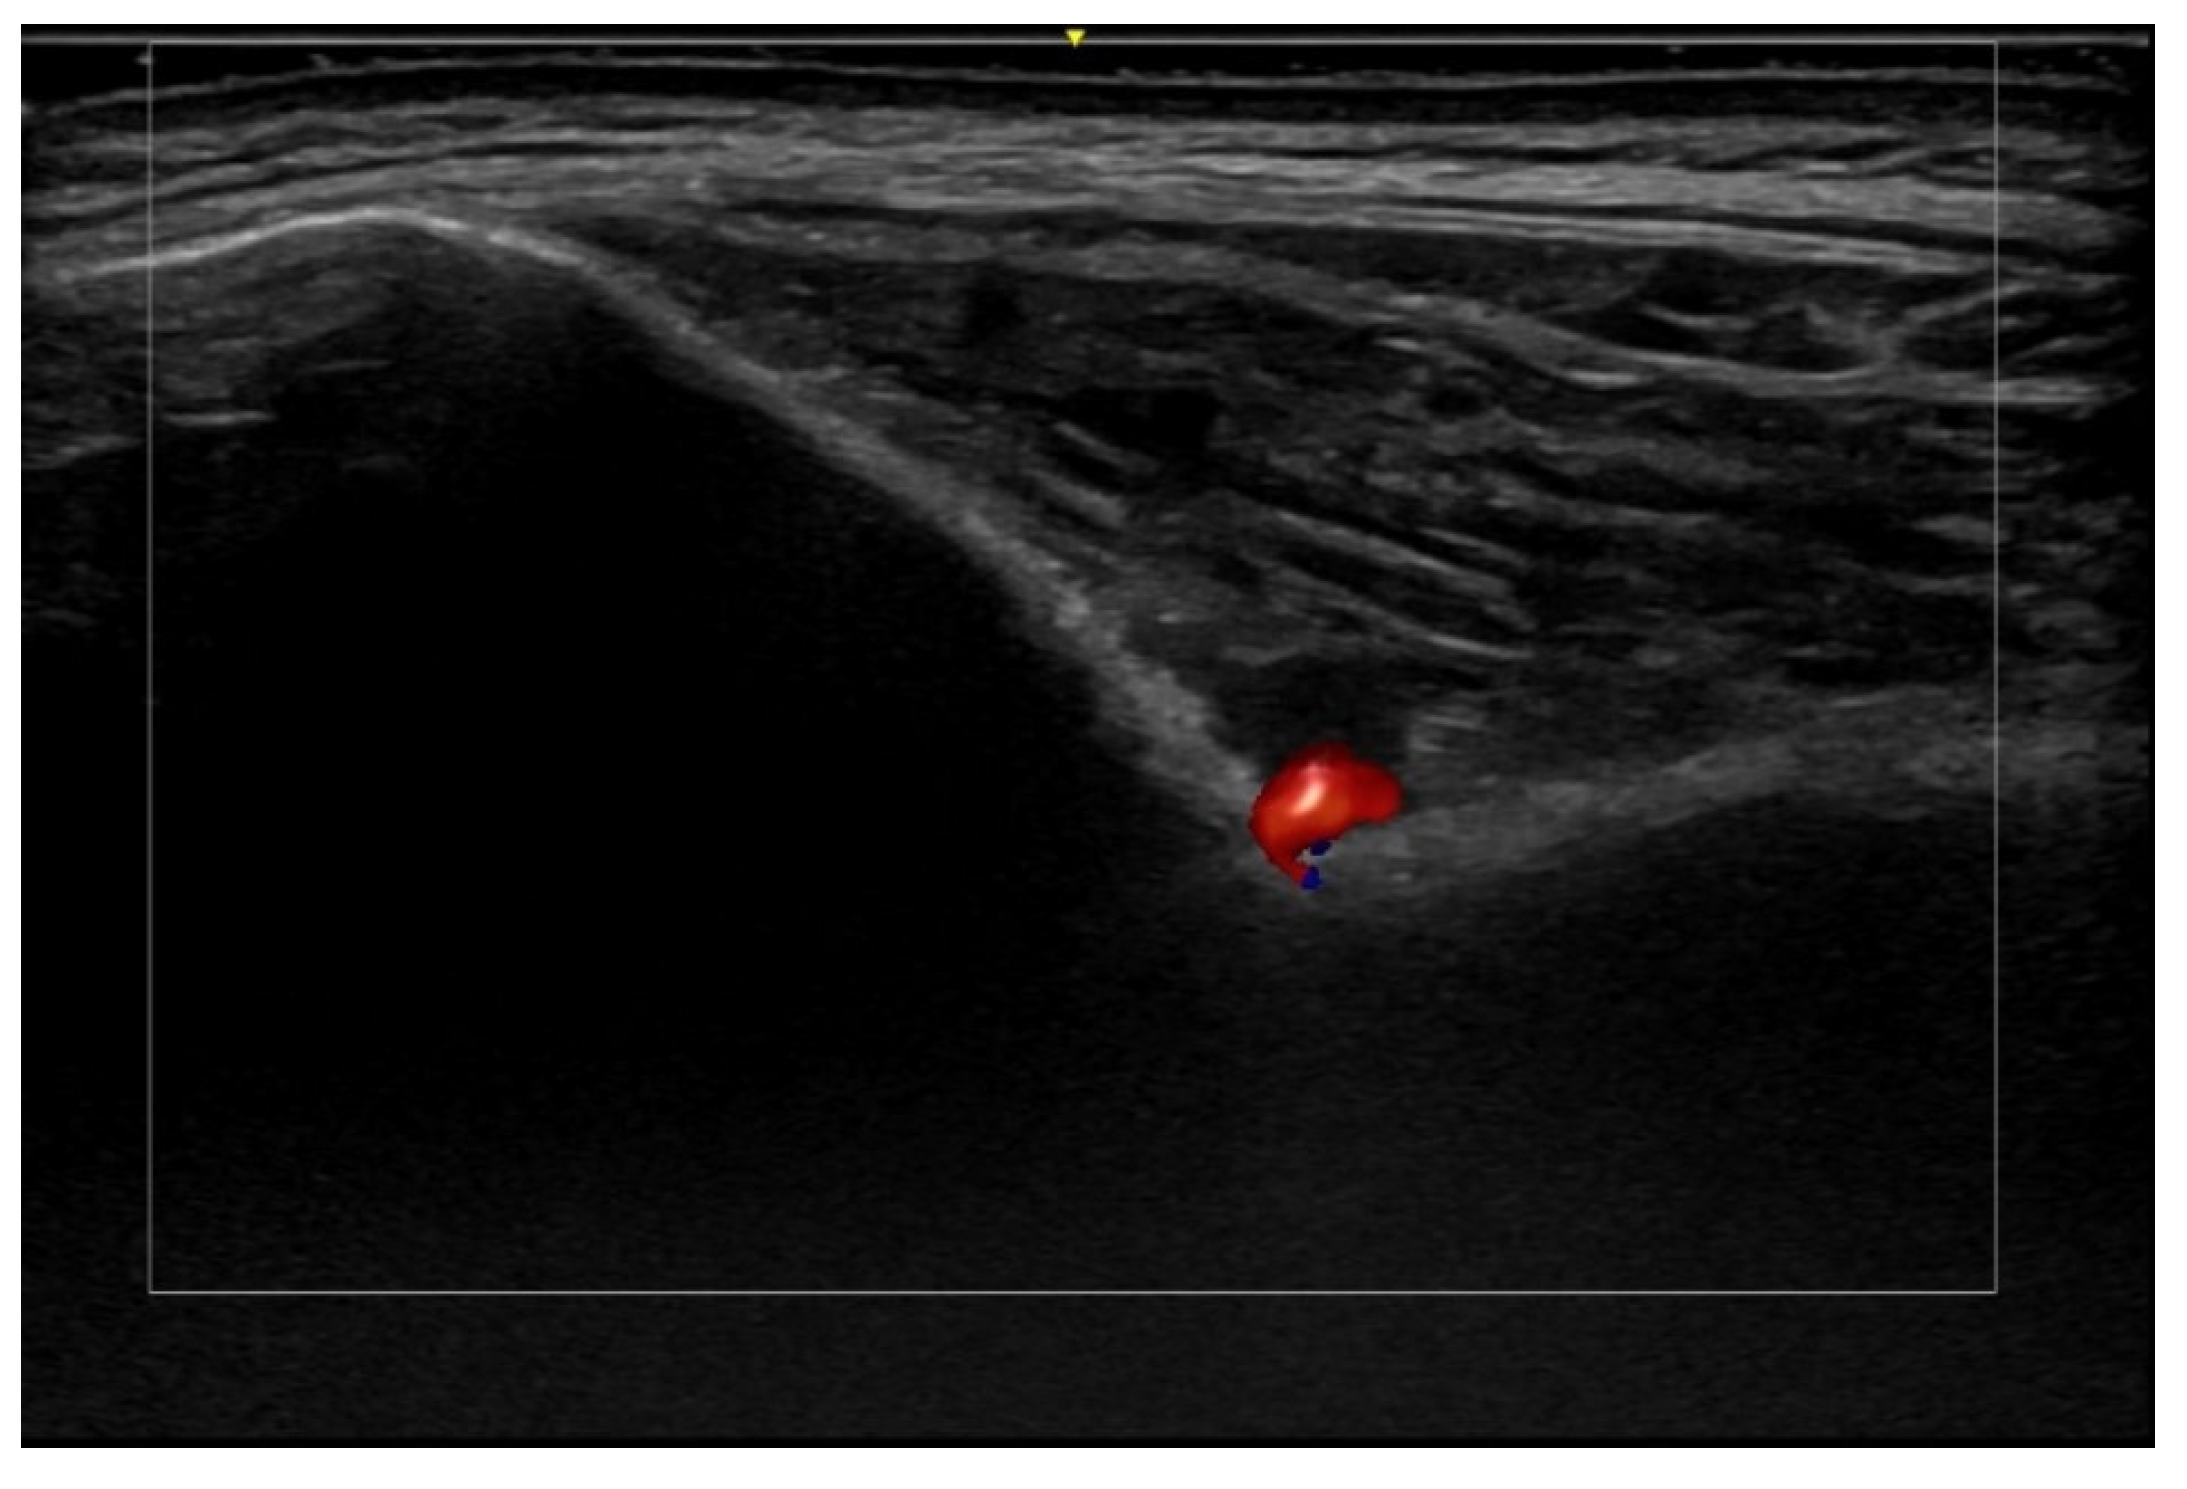

- Velthuis, P.J.; Jansen, O.; Schelke, L.W.; Moon, H.J.; Kadouch, J.; Ascher, B.; Cotofana, S. A Guide to Doppler Ultrasound Analysis of the Face in Cosmetic Medicine. Part 1: Standard Positions. Aesthetic Surg. J. 2021, 41, NP1621–NP1632. [Google Scholar] [CrossRef]

- Vasconcelos-Berg, R.; Izidoro, J.F.; Wenz, F.; Müller, A.; Navarini, A.A.; Sigrist, R.M.S. Doppler Ultrasound-Guided Filler Injections: Useful Tips to Integrate Ultrasound in Daily Practice. Aesthetic Surg. J. 2023, 43, 773–783. [Google Scholar] [CrossRef]